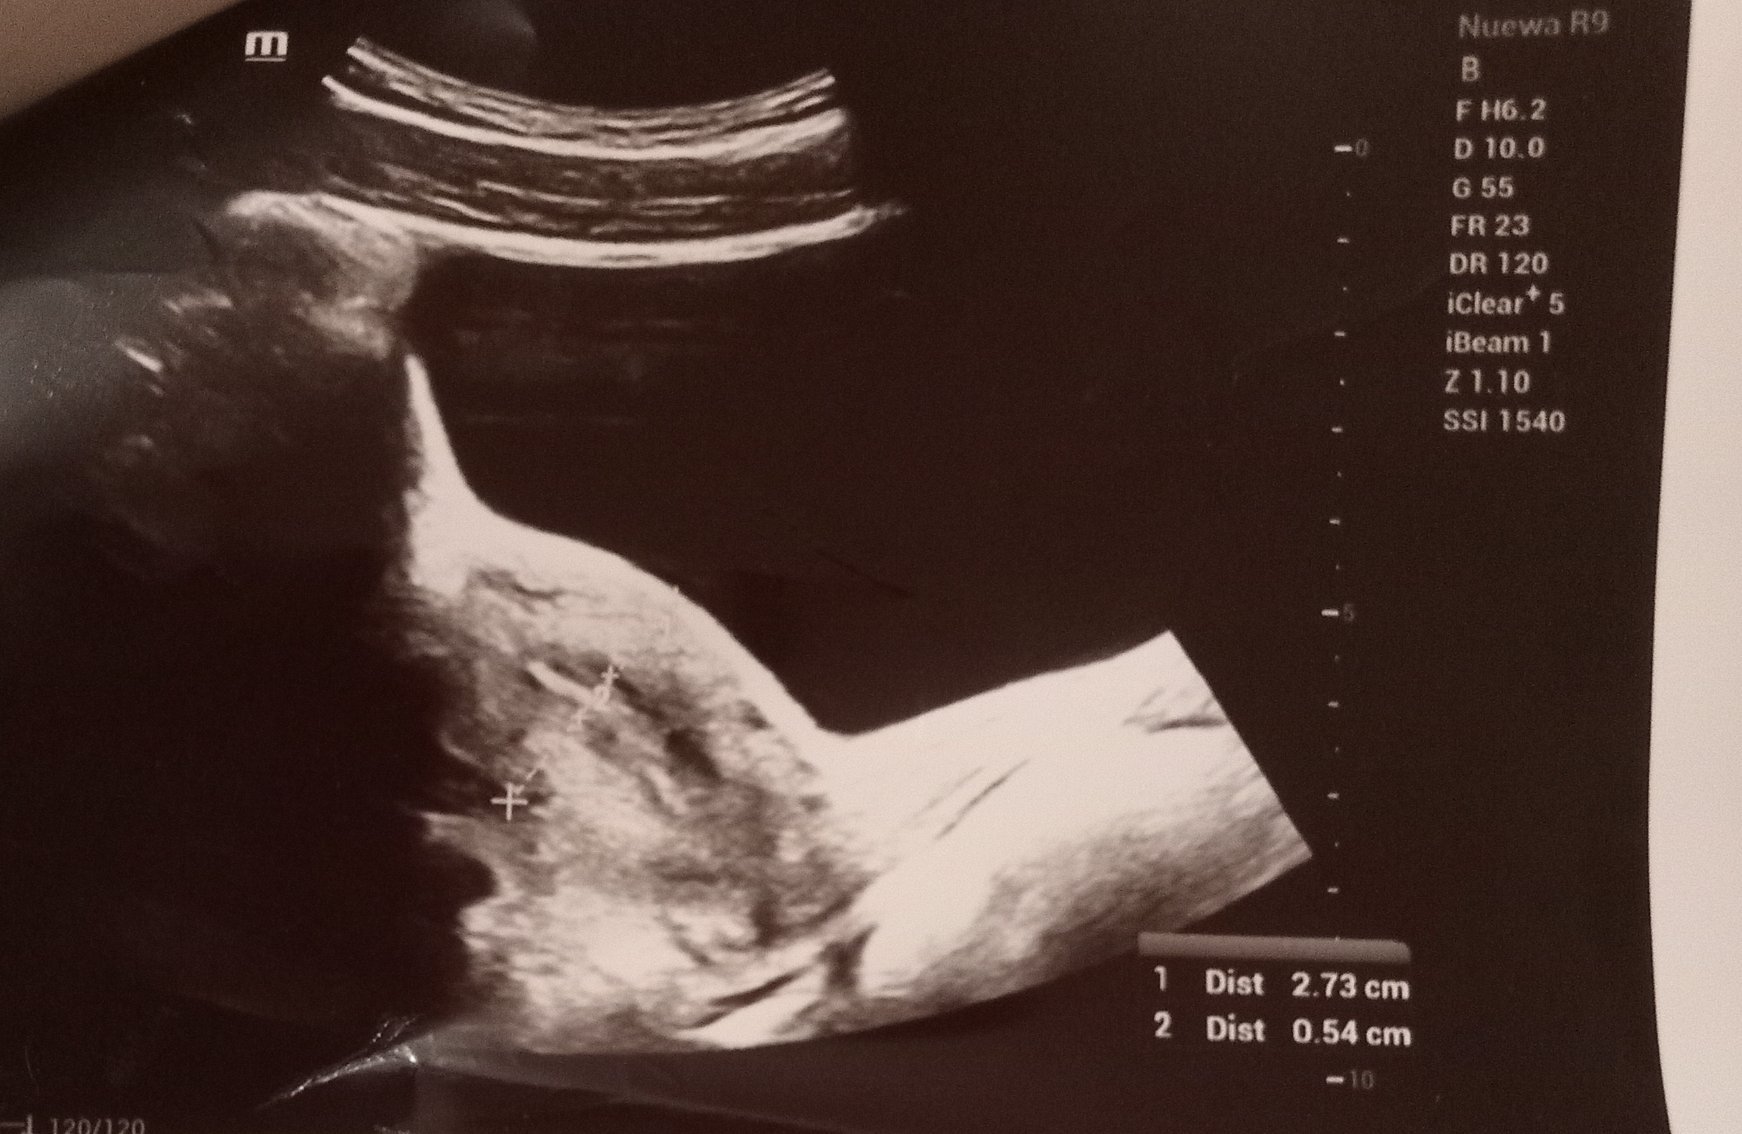

Ето и снимките от ехографа, какво мислите?

Скрит текст:

.